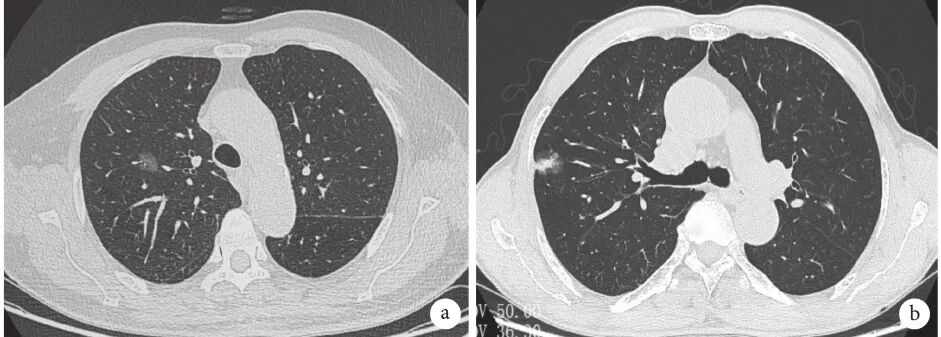

肺磨玻璃结节(ground-glass nodule,GGN)是体检或偶发早期肺癌的主要表现形式,常见于年轻、女性和不吸烟人群,正确的随访与处理策略可在降低肺癌死亡率的同时避免过度治疗。持续存在的GGN大多数为腺癌或前驱腺体病变,但呈惰性生长或长期不生长,有条件的随访是十分安全的。GGN必须采取个体化诊治策略,在充分考虑浸润程度、动态变化、治疗疗效与并发症、患者身体状况及心态等因素后做出治疗决策。不同于其它类型肺癌的尽早治疗策略,GGN型肺癌治疗时间窗很宽,必须在充分考虑治疗利弊后确定治疗时机。 外科手术是主要根治手段,对表现为GGN的前驱腺体病变目前普遍采取亚肺叶切除及不清扫淋巴结的术式。鉴于绝大多数GGN型肺癌属于无转移的局部病变,对不宜或不愿外科手术者可考虑采用介入根治。一般采用经皮微波、射频及氩氦刀等消融技术进行介入根治,具有创伤小、对肺组织损伤轻、可多次操作及可同步活检等优点,现有的研究结果已证实了消融治疗的可行性。超声与导航引导下经支气管消融治疗肺结节的疗效已初步得到了证实,是介入根治GGN的新途径。 未来在GGN的治疗上,消融治疗有望与外科手术同等重要,根据病灶特点、部位及患者情况等来选择治疗方法,以求患者利益最大化。近几年来,消融治疗 GGN 的探索逐渐增多。本文将在进一步认识 GGN 的基础上,探索 GGN 的诊治策略,并从呼吸介入角度,介绍消融治疗在 GGN 中的应用。 关键词:磨玻璃结节;诊治策略;经皮消融;根治 【正 文】 肺部磨玻璃结节(ground-glass nodule,GGN)指高分辨率CT表现为肺内边界清楚或不清楚的直径(或最大径) ≤30 mm的圆形或类圆形密度增高阴影,但病变密度不足以掩盖其中走行的血管、支气管、小叶间隔等结构,可为单发或多发,不伴有肺不张、肺门及纵隔淋巴结肿大和胸腔积液。 随着影像技术的发展、肺癌筛查的普及,GGN的检出率明显上升,因其与肺腺癌密切相关而备受关注。近年来多个国家、地区开展了肺癌筛查研究并提示,肺癌高风险人群中GGN的发病率为2.0%~3.3%。国内有报道在普通人群筛查发现的肺癌中,84.8%~95.5% 的患者在影像学上表现为GGN。与传统观念中的肺癌好发人群不同,大量研究数据显示恶性GGN好发于年轻、非吸烟、女性。 目前GGN在筛查、随访、治疗策略等方面缺乏共识,手术仍是拟诊GGN型肺癌根本的治疗策略,尽管最佳术式还存在争议。随着介入消融技术的发展,其应用范围也在不断拓宽。近几年来,消融治疗GGN的探索逐渐增多。本文将从GGN认识上的进展、诊治策略及经皮消融技术根治GGN的现状与探索等方面展开。 GGN根据是否存在实性成分可分为:纯磨玻璃结节(pure GGN,pGGN)和混合磨玻璃结节(mixed GGN,mGGN),前者又被称为无实性结节,后者又被称为部分实性结节(图1)。GGN的病理基础是肺泡间隔增厚,或部分肺泡腔充满液体、细胞或组织碎片,因此GGN并非某病的特异表现,它既可见于浸润性肺腺癌、腺体前驱病变,又可见于局灶性间质纤维化、肺泡出血、炎症或细支气管上皮增生、细支气管周上皮化生等。持续存在的GGN是指结节至少持续存在3个月以上且复查时未变小或消失。应特别重视持续存在的GGN,因其多为恶性或有向恶性发展的潜能。Kim等报道有超过80%持续存在的GGN最终被诊断为腺癌或前驱腺体病变。Lim等的研究也发现,最大径≥10 mm持续存在的pGGN手术病理100%为腺癌或前驱腺体病变。 GGN型肺癌均为腺癌,多数学者认为是经有序的多阶段发展而来的。从影像上由pGGN发展为mGGN或实性结节。在病理学上,通常是由非典型腺瘤样增生(atypical adenomatous hyperplasia,AAH)到原位腺癌(adenocarcinoma in situ,AIS),再进一步发展为微浸润腺癌(minimally invasive adenocarcinoma,MIA)、浸润性腺癌(invasive adenocarcinoma,IAC)。 GGN是一种非特异性的影像学表现,但其影像特点对于判断病理性质帮助很大,多数GGN的影像与病理存在相关性。纯磨玻璃影被认为是AAH或AIS的表现,当pGGN<5 mm时多为AAH;介于5~30 mm,AIS的可能性最大。 但值得注意的是,即便是pGGN,少数可能是MIA,极少数甚至已是IAC,其中大部分为贴壁生长型,但也有少数呈非贴壁生长型。而对于mGGN,当实性成分直径<5 mm以MIA多见,≥5 mm则提示IAC的可能性较大。GGN病灶越大,实性成分越多,其恶性可能性越大,侵袭性越强。此外,结节的形态,边缘(毛刺征、分叶征、血管集束征)及内部结构特征(CT值、空泡征、支气管充气征等)也是鉴别良恶性、侵袭性的重要影像征象。 现有的研究数据表明40%~50%的GGN在随访3~4个月时消失,这些属于暂时性GGN,考虑为良性病变。持续存在的GGN虽然多为腺癌或前驱腺体病变,但长期随访多无变化,仅少数出现生长。Chang 等报道122个pGGN随访近5年,90.2%未见生长。日本国立癌症研究中心牵头的一项多中心前瞻性研究发现,在4.3年的平均随访期内,1 046例pGGN中仅6.6%发展为mGGN。与pGGN相比,mGGN在随访中出现生长的比率较高。Sawada等的研究发现24.2%的mGGN在5年随访期内生长,远高于pGGN的12.8%;而且实性成分占比(consolidation/tumour ratio,CTR) 越高,生长的可能性越大,CTR 0.1~0.25、0.26~0.5、>0.5的mGGN随访5年的生长率分别为14.2%、28.6%、30.8%。GGN即使生长也呈惰性缓慢生长,倍增时间很长。根据研究报道mGGN的倍增时间是457~568 d,pGGN更是长达469~845 d。有研究数据表明,GGN的生长绝大多数发生在3~5年内。有一项研究报道CTR<0.5的108个GGN,平均随访4.2年,26.9%在随访期内增大,且均在随访3年内出现。Lee等报道了351个GGN随访10年的研究数据,发现后5年的GGN生长率不及前5年的1/3。对GGN生长规律的了解,有助于我们做出正确的处理策略,避免过度诊治。 如前所述,持续存在的GGN多数为腺癌或前驱腺体病变,根据影像特点是无法排除恶性病变的。因此,高分辨率CT发现GGN后如果3个月随访无缩小或消失就需要进行长期随访,直至可排除恶性。GGN生长缓慢或长期无改变,故随访期限一般至少5年。随访时间间隔应根据恶性风险及可能的浸润程度、患者的具体情况而定。 目前在国内外有许多相关的指南、共识,但由于各指南、共识制定者的专业背景、地域以及针对人群的不同,推荐的GGN随访策略差异较大。其中几个主要指南、共识的随访策略归纳见表1。指南及共识的策略差异导致了临床医生的困扰,但在临床工作中这些指南、共识只能提供参考,在对GGN的具体处理上应针对不同患者、病灶制定个体化的随访策略。 表1 国内外主要指南、共识对磨玻璃结节随访及处理的建议总结 我们结合长期的临床经验,提出以下几点供参考: GGN初次发现后均应3个月随访,大多数良性GGN会有缩小或消失; 首次随访无变化者应根据影像特征评估恶性风险及可能的病理类型,可疑AAH者可年度或2年后随访,可疑AIS者可6~12个月后随访,可疑MIA者 3~6个月后随访,可疑IAC者 3个月后随访或考虑活检、治疗; 后续随访时间间隔根据前一次随访评估的病理类型确定,在动态随访中如出现结节增大、实性成分增加或新出现恶性征象应缩短随访间隔或进行活检、治疗,如病灶持续稳定,可适当延长随访间隔时间; 必须结合患者身体状况及心态等因素来确定GGN的随访策略。对于预计生存期有限的高龄、合并严重慢性疾病患者,随访不宜过于积极,甚至可长期不随访;对于心态十分焦虑的患者,随访应相对积极。 GGN密度较低且存在正常的肺内血管,与实性结节相比非手术活检确诊率相对较低、出血风险较大,同时对恶性的浸润程度判断也欠准确。然而,非手术活检仍是GGN除外科手术以外唯一的确诊手段,具有明确病变性质以便对因治疗、避免外科误切、缓解患者心理压力等作用。因此,严格筛选非手术活检的适应人群及充分掌握活检技术也是GGN诊治策略的重要一环。 GGN非手术活检的主要适应证包括:有典型恶性特征但不愿或不宜外科手术、疑诊为可经内科治愈但病因不明的良性疾病、同时存在类似的多发结节且不能排除恶性;且均必须通过评估确认非手术活检可取到合格标本。活检途径分为经皮及经支气管两种,前者宜用于无支气管相通、活检部位无明显血管的病灶,后者则主要用于与支气管管腔相通的结节病灶。经皮穿刺活检是肺结节诊断的传统有效技术,报道的GGN诊断率约64.6%~93%。对≤1 cm的GGN确诊率差别更大,48.5%~87%不等。近来,经引导鞘管超声支气管镜(endobronchial ultRASonography with a guide sheath,EBUS-GS)及导航技术的应用,大大提高了GGN经支气管活检的确诊率及安全性,其阳性率达到57%~69%,病灶越大阳性率越高,而且高分辨率CT可见支气管与病灶中间相通者确诊率更高。冷冻活检能够取到较大的标本,有望明显提高诊断率。有研究[49]报道EBUS-GS联合超细探头冷冻肺活检诊断率可达到82.61%,且诊断率与病灶大小、CTR、是否采用导航或X线透视等因素无关,值得进一步探索。 除非高度怀疑真菌感染或浸润性肺癌,一般需在随访3个月以上才考虑活检,以避免不必要的活检。 GGN病灶及其周围存在正常肺部血管,经皮穿刺活检进针及活检切割时必须尽量回避较大血管,防止大出血。 pGGN经皮穿刺活检阳性率较低且出血风险大,必须慎用。 如病灶部位血管丰富,于微波或射频热消融中或消融后进行经皮穿刺活检可减少出血量、提高安全性,且不影响活检的病理检查结果。 为提高诊断率及减少并发症,经支气管镜活检应该在超声探头可探及病灶的前提下进行,冷冻肺活检最好在X线实时透视下采用细探头取材。 外科手术切除是拟诊恶性GGN的主要治疗方法。《上海市肺科医院磨玻璃结节早期肺腺癌的诊疗共识(第一版)》中对可疑AIS、MIA及IAC的GGN的手术指征做了较为详细的说明,但病理类型仅通过影像特征分析得出,存在不准确的可能性。 目前相对比较一致的观点是当多学科会诊后高度怀疑IAC病变时,应手术干预。对于影像特征怀疑为AIS或MIA时,需要根据病变部位、随访时间长短、发展为浸润病变的概率等因素综合考虑。GGN型肺癌是一种惰性的肿瘤,有条件随访十分安全,治疗窗口期很长。因此,对前驱腺体病变不应过早积极手术干预,以避免过度治疗。另外,是否考虑手术治疗必须结合病灶部位、结节数量、患者的预计生存期及心态等,对于非优势部位、双侧多发、高龄或有严重基础疾病者手术宜消极,反之则可积极考虑手术治疗,当患者对GGN十分焦虑时手术指征也可适当放宽。 随着临床研究的深入,临床医生对GGN的切除范围有了更准确的认识。基于1995年的一项随机对照研究(RCT),肺叶切除被认为是早期肺癌的标准术式。然而对于肺结节病灶,尤其是近几年来备受关注的GGN型肺癌,最佳的切除范围还存在争议。切除范围的选择,需要综合考虑病灶影像特征及部位、患者年龄及心肺功能等因素。日本的Ⅱ期临床研究JCOG0804/WJOG4507显示,对最大径≤2 cm,CTR≤0.25的GGN型肺癌进行足够切缘的亚肺叶切除,5年无复发生存率达99.7%。美国国立综合癌症网络(NCCN)指南已推荐亚肺叶切除可用于最大径≤2 cm,CTR<0.5的外周GGN(2类)。而对于CTR>0.5的病灶,其术式的选择仍存在争议。参考NCCN指南的建议,对于CTR>0.5的mGGN,在患者可耐受的情况下仍优先考虑肺叶切除。但近年来国内外开展了一些研究,试图探索这部分患者的最佳术式,也提出了新的观点。国内有临床研究报道,CTR>0.5的mGGN行肺段切除与肺叶切除的5年无复发生存时间相仿。 另有两项针对直径≤2 cm mGGN的RCT正在进行(日本的JCOG0802和美国的CALGB140503),从JCOG0802已报告的部分研究结果来看,对于最大径≤2 cm、CTR>0.5的mGGN,肺段切除无论是总生存率还是肺功能保留方面都优于肺叶切除,但还需待其最终研究报道。尽管如此,目前支持亚肺叶切除用于CTR>0.5 的mGGN的证据尚不足,有待进一步研究。除了病灶大小、CTR外,术中冰冻病理可以辅助GGO病灶的术式选择。有一项纳入803例Ⅰ期肺腺癌患者的研究发现,术中冰冻病理判断AIS、MIA、IAC的准确率可到达96%。对于术中病理为AIS、MIA的GGN行亚肺叶切除,5年无复发生存率达100%。 为达到术中创伤最小化及术后生存期最大化的目的,外科学者也在不断探索GGN型肺癌术中淋巴结的处理方式。多项研究结果提示GGN的淋巴结转移率很低,pGGN的淋巴结转移率为0,CTR<0.5的mGGN其淋巴结转移率0~6.9%。Moon等的研究提示肿瘤大小和CTR是淋巴结转移的独立预测因素。一项纳入129例CTR<0.5的GGN患者的回顾性研究发现,无论是否进行淋巴清扫、采样,患者的5年无复发生存率无差异。还有类似的研究也提示,对于CTR<0.5的GGN,淋巴结清扫与否并未影响患者的预后。根据2021年NCCN指南的建议,对于最大径<2 cm,CTR<0.5的外周GGN,技术允许情况下需进行N1、N2淋巴结采样。而对直径>2 cm或CTR>0.5的GGN,目前更为推荐系统性淋巴结清扫。此外,术中冰冻病理也是淋巴结处理方式的重要参考指标。有研究结果提示,对于术中冰冻病理为AIS及MIA未进行淋巴结清扫,其5年无复发生存率可达100%。考虑到AIS及MIA不发生淋巴结转移,《上海市肺科医院磨玻璃结节早期肺腺癌的诊疗共识(第一版)》指出,对于影像拟诊AIS或术中冰冻初步诊断为MIA,不需要进行淋巴结清扫或采样。基于目前的研究结果,我们认为在进行术式选择时不能一概而论,要充分考虑GGN的大小、形态、位置、CTR等因素,参考术中冰冻病理结果,选择可根治、创伤小、尽量保留肺功能的术式。 除了外科手术,立体定向体部放疗(stereotactic body radiation therapy,SBRT)及消融技术介入治疗也是肺结节的治疗手段。SBRT可用于经多学科联合诊疗认为不能耐受外科手术的早期肺癌。然而,GGN病灶存在剂量传递及实时影像引导难以实行等问题,关于SBRT治疗GGN的研究甚少。有项单臂回顾性研究提示SBRT治疗GGN型肺癌可获得较好的局部控制。另外还有少数SBRT治疗早期肺癌的研究中包含少量GGN病灶,提示磨玻璃病灶与更好的预后相关。但目前缺乏足够的证据支持SBRT用于拟诊GGN型肺癌的治疗。 肺癌的经皮介入治疗技术主要包括热消融如射频消融(radiofrequency ablation,RFA)、微波消融(microwave ablation,MWA),冷冻消融如氩氦刀冷冻消融(argon-helium cryoablation,AHC)以及放射性粒子植入等,目前临床常用于早期肺癌的消融技术是经皮RFA、MWA 、AHC等。 RFA是目前治疗实体瘤最为广泛的消融技术,也是应用于肺部肿瘤最早,经验最丰富的消融治疗手段。消融体积主要取决于局部射频产生的热传导与血液及细胞外液间的热对流,但其热沉效应明显,易受组织特性影响。在肺部,RFA主要适用于小到中等大的肺癌。近年来,RFA用于治疗不能耐受或拒绝手术的Ⅰ期肺癌的报道越来越多,结果提示其无复发生存或总生存与手术或SBRT相当。研究还显示RFA治疗早期肺癌的5年无进展生存率为40%~74%,而肿瘤大小是其预后的重要影响因素,<3 cm的肿瘤预后更佳。2013年美国胸科医师学会(ACCP)推荐RFA用于<3 cm且不适合手术的外周型Ⅰ期非小细胞肺癌。 MWA是将微波消融针(微波天线)穿刺到靶组织内产生微波能量,使肿瘤细胞凝固坏死。MWA具有肺内对流性更高、热沉效应更弱的特点,其消融范围较RFA大,而且所需的消融时间更短,耐受性更好。理论上MWA相较于RFA可能获得更好的肿瘤局部控制。近10年来,MWA治疗早期肺癌的研究也逐渐增多。一项纳入104例Ⅰ期非小细胞肺癌的研究发现,MWA治疗后的局部复发率为23%(中位随访时间47个月),而肿瘤>3.5 cm是局部复发的独立危险因素。而且该研究还对复发者再次进行MWA,这些患者与未复发者的生存结局相仿。该研究给了我们两点启发:首先是严格控制消融治疗的肿瘤大小,可以获得更好的局部无复发生存;其次是复发者可重复MWA治疗,其预后与未复发者一样。Han等的研究发现MWA治疗75岁以上早期肺癌患者的4年肿瘤特异性生存率为64.7%。一项2019年的多中心回顾性研究则发现,MWA治疗80岁以上老年早期肺癌患者的5年局部控制率为63.9%。Wang等的对照研究进一步发现,肺叶切除与MWA治疗的2年无疾病生存率分别是75.29%和76.09%,尽管在该研究中两种治疗的预后相仿,但MWA的治疗花费明显低于肺叶切除。 AHC是通过高压氩气使组织迅速降温至–140℃,再通过氦气使组织升温到20℃~40℃,温度变化使得靶组织蛋白质变性、细胞裂解、组织缺血坏死等。AHC可以达到与MWA相当的消融范围,而且具有更好的保留细胞结构、对周围组织损伤小、操作过程中可清晰观察到消融边界等优点,其主要的缺点是操作时间相对较长。同RFA及MWA一样,AHC也推荐用于3 cm以内病灶的消融治疗。近年来关于冷冻治疗早期肺癌的研究也逐渐兴起。Yamauchi等对22例接受AHC治疗Ⅰ期肺癌患者进行回顾性研究,发现随访期内仅3%病灶出现进展,平均无进展时间为(69±2)个月,3年无疾病生存率67%。Moore等的研究结果显示AHC治疗Ⅰ期非小细胞肺癌的5年无进展生存率可达87.9%±9%。Zemlyak等的研究则对比了亚肺叶切除、RFA及AHC治疗早期肺癌的疗效,结果显示亚叶肺切除与AHC的3年肿瘤特异性生存率分别是90.6%和90.2%。以上研究提示经皮AHC治疗早期肺癌的局部复发率低,总生存率与亚肺叶切除相当。 目前,关于经皮消融治疗早期肺癌的研究越来越多,而且大多取得不亚于手术切除或SBRT的疗效。值得注意的是,在手术仍是早期肺癌主流治疗的大环境下,消融治疗的作用可能被低估。因为接受局部消融治疗的患者往往年龄更大、肺功能更差、体力活动状态(PS)评分更高。而这是消融治疗面临的普遍问题。一项单中心的回顾性研究较清晰地阐明了这种情况,该研究回顾性对比RFA、SBRT及亚肺叶切除治疗Ⅰ期肺癌患者的5年总生存率和无进展生存率,结果分别是RFA 58.9%和39.3%、SBRT 42.0%和34.9%、亚肺叶切除 85.5%和75.9%,而这明显的差距却在矫正了PS评分等因素后消失了。 GGN能否通过消融治疗达到根治?要回答这个问题需要明确以下两点:GGN型肺癌是否存在转移、能否当作局部疾病进行治疗?消融技术介入治疗GGN病灶能否达到根治? 有关GGN型肺癌的转移问题关键要看是否存在淋巴结转移,相关的研究数据报道较多。Zha等的一项纳入867例GGN型肺癌的研究显示,pGGN、CTR<0.5 mGGN、CTR 0.5~0.79 mGGN的淋巴结转移率分别为0%、6.9%、9.1%。而在Ye等的研究中,淋巴结转移率 pGGN为 0%、mGGN为 2.2%,均远低于实性结节的27%。一项回顾性研究纳入了581例GGN型肺癌,其中145例CTR≤0.5、最大径≤3 cm的GGN均未见淋巴结转移,而且该研究中27例0.5<CTR<1.0、最大径≤1 cm的GGN型肺癌也未见淋巴结转移。综合大量的研究数据可发现,pGGN均未见淋巴结转移,CTR≤0.5或最大径<1 cm的mGGN淋巴结转移率极低,而CTR>0.5或最大径>1 cm的mGGN淋巴结转移率也明显低于实性结节。从病理角度,AIS和MIA阶段没有淋巴结转移,即便是IAC,如果CTR≤0.5也极少有淋巴结转移。另外,GGN型肺癌未见远处转移的报道,不少专家提出GGN型肺癌无需行头颅磁共振成像(MRI)、骨扫描、支气管镜等检查评估。综上,绝大多数GGN型肺癌属于无转移的、可经局部治疗治愈的局部病变,提示局部消融治疗有根治该类疾病的可能性。 那么,消融治疗GGN病灶能否达到根治呢?消融治疗在早期肺癌中的成功应用,也促进了它在这一特殊类型早期肺癌中的探索。GGN型肺癌属于3 cm以内早期肺癌或原位癌,理论上看可根治实性早期肺癌的消融技术也完全有可能根治GGN型肺癌。尽管目前消融技术根治GGN的报道并不多,但均取得了令人满意的结果。Kodama等的回顾性研究发现,接受RFA治疗的42例GGN型肺癌患者中位随访时间42个月,5年总生存率和肿瘤特异性生存率分别为96.4%和100%。Iguchi等纳入16例GGN型肺癌患者进行RFA治疗,中位随访时间61.5个月,3年的病灶控制率达92.3%,且未发现严重并发症。我国的一项回顾性研究也观察到了RFA治疗GGN型肺癌的近期疗效,半年的病灶控制率100%。2018年一项回顾性多中心研究纳入了51例接受MWA治疗的GGN型肺腺癌患者,技术成功率100%,3年无局部进展生存为98%,3年肿瘤特异性生存率为96%,并发症均在可控范围。2020年也有一项回顾性研究报道了MWA在多发GGN中的应用,技术成功率100%,中位随访18个月未发现肿瘤复发,但该研究随访时间较短。2015年Kim等报道了1例AHC治疗5 mm pGGN的成功病例。2019年有一项小样本回顾性研究[101]纳入14例接受AHC治疗的GGN型肺癌,结果显示随访2年未见复发且无严重并发症。 以上研究结果为消融治疗GGN提供了初步的循证医学证据,提示通过消融技术介入根治GGN型肺癌是可行的,且操作安全。需要指出的是,这些临床研究的随访时间相对较短,病例数较少,尚缺乏大样本、前瞻性临床研究的数据。相信未来会有更多大样本、多中心、前瞻性、长随访的研究,以提供高级别循证医学证据。而且,虽然消融治疗有根治大部分GGN型肺癌的可能,但其无法进行淋巴结清扫或治疗,所以并不意味着消融治疗可以替代外科手术。本中心也对一些符合条件的GGN型肺癌病例进行了经皮消融治疗,积累了一定的经验,在临床中验证了GGN介入根治的可行性,典型病例见图2~4。 图3 CT引导经皮射频消融治疗磨玻璃结节典型病例 男,78岁,右肺下叶GGN经皮穿刺活检确诊腺癌,肾功能不全不宜外科手术;a:治疗前右肺下叶1.0 cm的mGGN;b:单极射频消融治疗GGN;c:射频消融治疗1个月后影像表现;d:射频消融治疗35个月后病灶仅残留纤维条索影 女,31岁,两肺多发GGN,右肺上叶mGGN经支气管镜活检确诊为腺癌,拒绝手术;a:治疗前右肺上叶1.6 cm的mGGN;b:氩氦刀冷冻消融治疗;c:冷冻治疗10 d后影像表现;d:氩氦刀术后18个月病灶吸收仅残留少许纤维条索影 作为外科手术的有力补充,消融技术介入根治的临床应用适应证有哪些?目前尚未发布针对GGN介入根治的临床指南,仅有国内今年发布的专家共识。该共识提出的GGN消融治疗适应证可供临床应用时参考,包括: 病理证实为AAH、AIS、MIA、IAC(排除远处转移)的周围型GGN,且存在因心肺功能差或高龄等因素无法耐受手术、术后出现新病灶无法耐受再次手术、拒绝手术、多发GGN、重度焦虑等; 拒绝活检及手术的患者如有影像学恶性征象或极度焦虑,在多学科会诊的基础上与患者共同决策确定是否“可不取病理直接消融或消融与活检同步进行。”总之,鉴于目前尚缺乏高级别循证医学证据及权威指南的推荐,消融治疗应严格掌握适应证,只针对不能耐受或不愿意外科手术的患者,作为外科手术的补充。 我们结合10余年来经皮介入消融的经验,提出以下补充建议: GGN的非手术活检不能准确判断肿瘤的浸润程度,活检的病理分型只能作参考,但一般不会影响适应证的选择。 无病理确诊GGN的消融治疗适应证除了拒绝活检及手术外,还应包括经评估非手术活检难以取到合格标本或出血风险大的患者,如1 cm以内的pGGN、中间有大血管的GGN等。 选择消融治疗时必须先评估病灶所在位置对消融疗效的影响,为确保根治,病灶必须位于治疗针易于到达且周围无心脏、大血管的部位。 不能耐受手术主要包括高龄或有严重并存病、多发结节、近肺门区结节等,注意不宜手术是相对的,外科、内科、介入科医生的看法可能存在较大的差异;不愿意手术必须以经充分说明后患者及家属仍签字拒绝手术为准。 对病理未确诊的GGN,考虑到pGGN活检的病理结果准确性较差且活检后出血较明显,宜不取病理直接消融;消融同步活检主要应用于病理未确诊的mGGN,活检可在消融前、消融中或消融后进行。对血管丰富的病灶,建议采用热消融如微波或射频,且消融中进行活检为佳,有助于减少活检后出血且不影响活检的病理结果;不建议在消融后活检,因有学者提出热消融造成的组织碳化可能会影响活检的病理检查结果。消融后活检主要应用于冷冻消融时,因冷冻不会影响活检标本的病理结果。 与外科手术一样,确定消融治疗的时机需要充分考虑GGN生长规律及侵袭性。GGN型肺癌呈惰性生长,治疗时间窗很宽,为避免过度治疗,必须是经过一段时间的随访后高度怀疑为浸润性病变、或随访中病灶增大或实性成分增多时才考虑消融介入根治。另外,对十分焦虑的患者在考虑消融治疗时可积极些,对预计生存期有限的高龄或有严重并存病患者,必须在充分衡量得失后确定是否消融。消融介入治疗能否达到根治,也与操作者的操作技术及临床经验密切相关。建议MWA、RFA采取低功率、较长时间的治疗策略,确保消融后磨玻璃影大于病灶10 mm以上;氩氦刀冷冻治疗尽量采用多针适型,分2~3个循环、冷冻总时间不短于30 min,确保冷冻消融治疗中病灶位于–40℃范围内。 相较于外科手术,经皮消融介入根治GGN具有操作快速、创伤小、安全性高、费用低,对肺组织损伤轻、可多次操作,对无病理诊断者可同步活检等优点。但也存在对操作技术要求高、消融治疗参数个体差异大、质量控制要求高、较难同质化、不能百分之百确保根治等缺点。目前经皮消融根治GGN是可行的,临床主要用于不宜或不愿手术的GGN型早期肺腺癌或病理未确诊但高危的GGN。鉴于pGGN及绝大多数mGGN属于没有转移的局部疾病,未来经皮消融治疗有望成为这类患者除了外科手术以外的主要治疗手段,根据病灶特点、病灶部位及患者情况等个体化选择治疗方法。 此外,气道内超声及电磁、虚拟导航技术的快速发展使经支气管消融治疗GGN成为可能。近年来,导航技术及超声引导下插入RFA、MWA软性探头消融治疗恶性肺结节已在不断探索中,带有水微循环的经支气管镜软性消融探头也已研发成功,拓展了消融治疗范围。目前为数不多的单中心小样本的研究也初步证实了支气管镜下消融疗效确切。但该技术仍存在许多问题: 消融探头难以经病灶中间到达病灶远端,消融范围难以确保超过病灶边缘10 mm以上。 探头只能经支气管到达病灶,只能应用于消融探头能够到达的与支气管相通的病灶;支气管镜下经肺实质结节抵达术(BTPNA)可使消融电极不经支气管到达病灶部位,但该技术存在操作难度大、创伤较大、费用高、费时长等缺点。 消融治疗功率不稳定,且没有标准的消融治疗参数可供参考,影响了消融效果及该技术的普及。 设备昂贵、消融探头没有取得管理部门批准,目前只能临床科研中应用。总之,作为肺结节消融治疗的新技术,经支气管消融技术目前可探索性的应用于治疗肺功能差、经皮穿刺气胸或出血风险大的恶性GGN或实性结节。随着治疗探头更加精细、输出功率更加稳定以及BTPNA的改进、应用经验的累积,该技术将逐渐成熟,有望扩大适应证及提高根治的可能性。 一、磨玻璃结节再认识